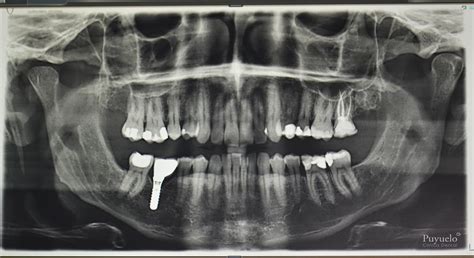

- Colocación de implantes

En una radiografía panorámica se pueden ver todas las piezas dentales, incluyendo aquellas que aún no han erupcionado completamente.

Gracias a su capacidad para identificar una amplia gama de problemas dentales y maxilofaciales, las radiografías panorámicas son un pilar en la planificación y diagnóstico odontológico. En conjunto, una radiografía panorámica ofrece una visión detallada que permite diagnosticar diversas condiciones dentales, desde caries hasta problemas de las encías y anomalías en la posición de los dientes.

Algunas de las condiciones que se pueden detectar incluyen:

- Las caries que se forman entre los dientes o debajo de empastes antiguos pueden pasar desapercibidas durante un examen visual.

- La pérdida de hueso alrededor de los dientes, uno de los principales indicadores de la periodontitis, es fácilmente visible en una radiografía panorámica.

- Las radiografías panorámicas son especialmente útiles para diagnosticar dientes incluidos o retenidos, es decir, aquellos que no han erupcionado completamente o que están atrapados en el hueso.

- Esta técnica es especialmente útil para detectar quistes dentales, tumores benignos y otros problemas óseos que podrían pasar desapercibidos.